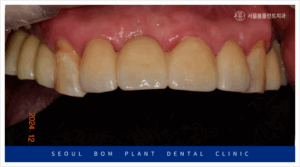

앞니도 어금니와 마찬가지로

심미성이 높은 지르코니아

보철물로 수복해 드리면서

모든 치료를 마무리해 드렸는데요.

환자분께서는 임플란트를

사용하실 때보다

훨씬 더 심미적여서

마음에 드신다고 말씀해 주셨으며,

양측 어금니의 식사가 가능해져

만족해 하셨는데요.

치아의 소중함을 깨달으시고

앞으로 관리를 잘 해주시겠다고

약속해 주셨답니다.